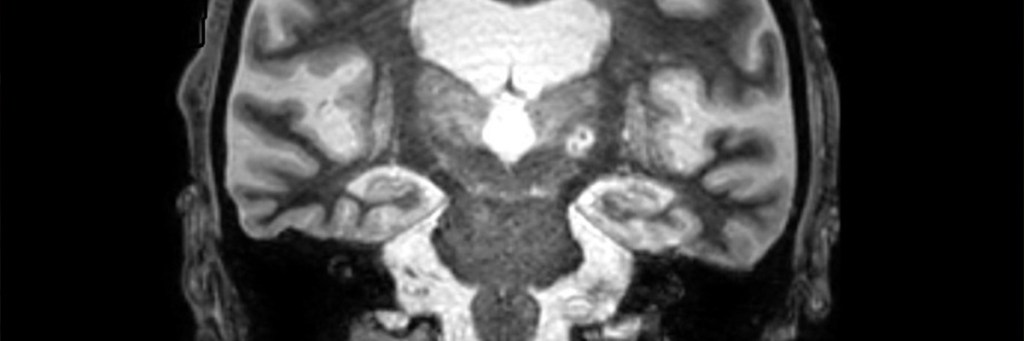

Cada año, casi 800.000 personas en los EUA sufren un accidente cerebrovascular, que ocurre cuando el flujo sanguíneo a áreas específicas del cerebro es insuficiente, lo que provoca la muerte de células cerebrales debido a la falta de oxígeno. Si bien la resonancia magnética (IRM) es una herramienta de diagnóstico valiosa para el accidente cerebrovascular, los retrasos en el tratamiento pueden conducir a peores resultados. En 2016, la FDA aprobó una nueva terapia para los trastornos del temblor, que implica ultrasonidos focalizados de alta intensidad (HIFU) para apuntar y destruir una parte del tálamo, un área del cerebro a menudo responsable de los temblores. Un estudio reciente ha demostrado que una molécula conocida como proteína ácida fibrilar glial (GFAP) aumenta significativamente en la sangre de los pacientes sometidos a tratamiento HIFU para temblores, lo que causa daños similares a los de un pequeño accidente cerebrovascular. Este hallazgo, publicado en Brain Communications, sugiere que la GFAP podría ser un biomarcador prometedor para el accidente cerebrovascular y eventualmente puede conducir a análisis de sangre para el diagnóstico rápido de lesiones cerebrales.

En 2022, investigadores del UT Southwestern Medical Center (Dallas, Texas, EUA) informaron sobre una técnica que mejoraba la focalización del HIFU para el tratamiento del temblor. Recientemente, el equipo notó que la lesión cerebral controlada causada por esta terapia parecía similar a un accidente cerebrovascular en las imágenes cerebrales, y que ambos tipos de daño compartían características, en particular en la forma en que el cerebro responde a estas lesiones. Los investigadores plantearon la hipótesis de que esta similitud podría ayudar a lograr el objetivo largamente buscado de diagnosticar accidentes cerebrovasculares y lesiones cerebrales a través de marcadores sanguíneos. Los intentos anteriores se han enfrentado a desafíos como la falta de muestras de sangre tomadas antes de un accidente cerebrovascular, las diferencias en la ubicación de las lesiones cerebrales en los pacientes con accidentes cerebrovasculares, la incertidumbre en torno al momento en que se producen los accidentes cerebrovasculares y las variaciones entre los pacientes.